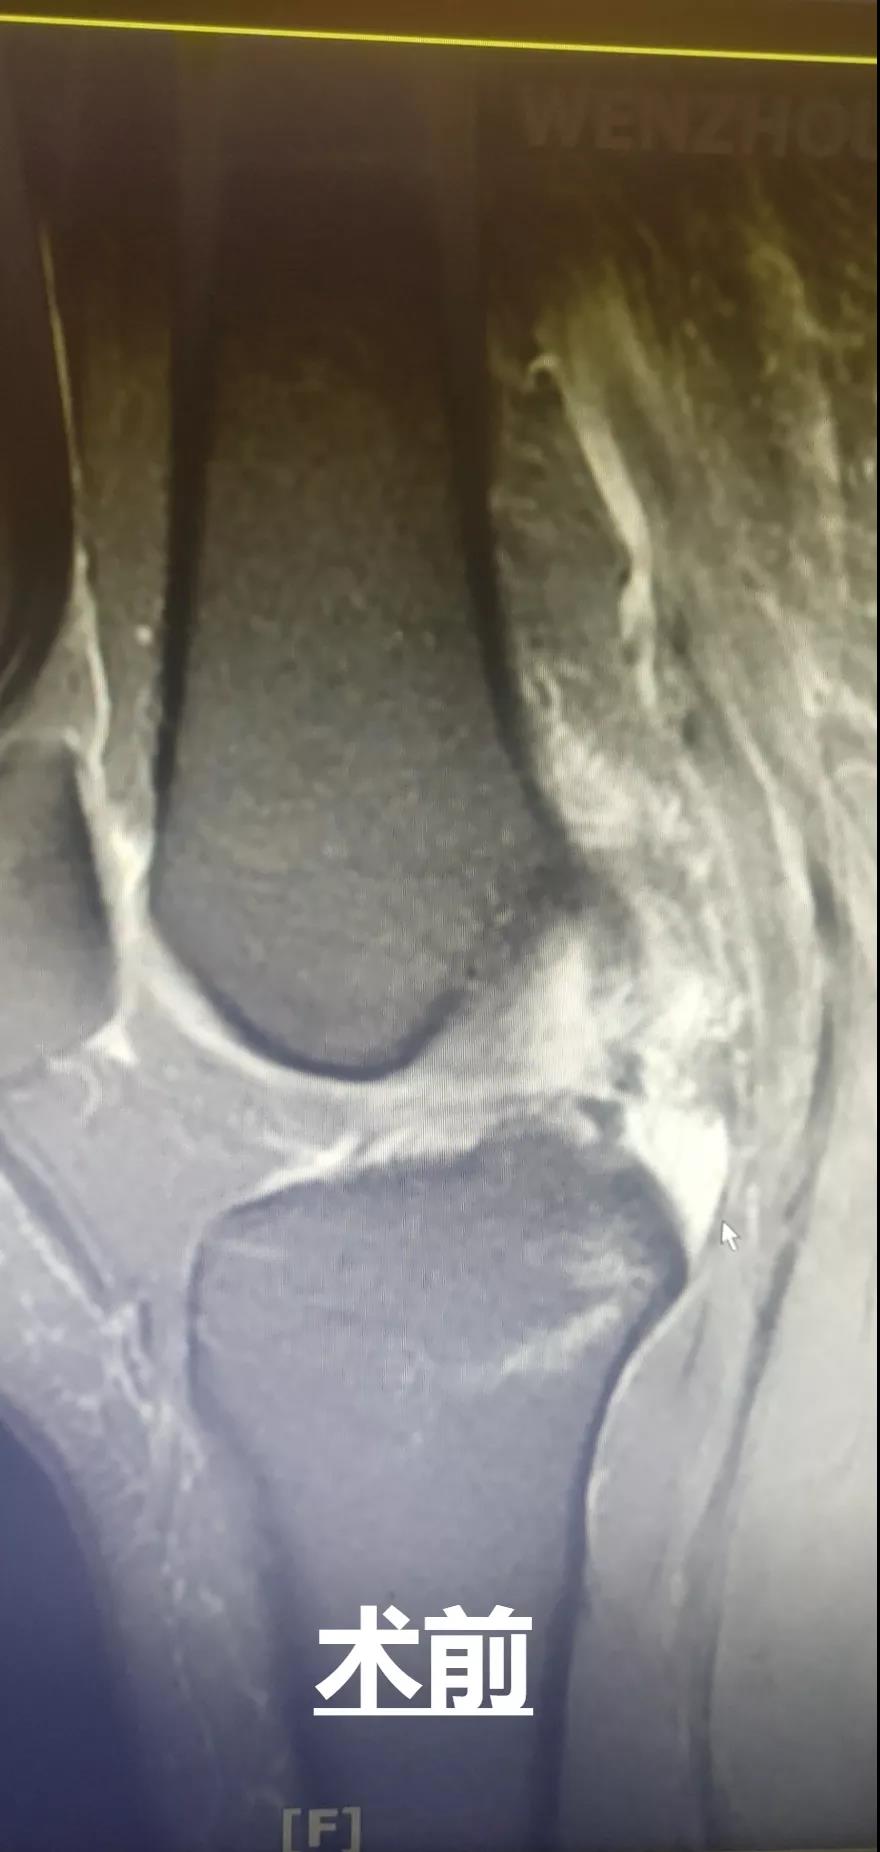

此外,和平國(guó)際醫(yī)院關(guān)節(jié)鏡微創(chuàng)團(tuán)隊(duì)還完成了一例交叉韌帶修復(fù)術(shù)。此手術(shù)采用三個(gè)約0.5cm的微小創(chuàng)口,于脛骨結(jié)節(jié)處進(jìn)行定位,后鉆通脛骨隧道,應(yīng)用多種袢鈦板進(jìn)行多位置固定,手術(shù)過程短,創(chuàng)口小,術(shù)后效果好,患者十分滿意。